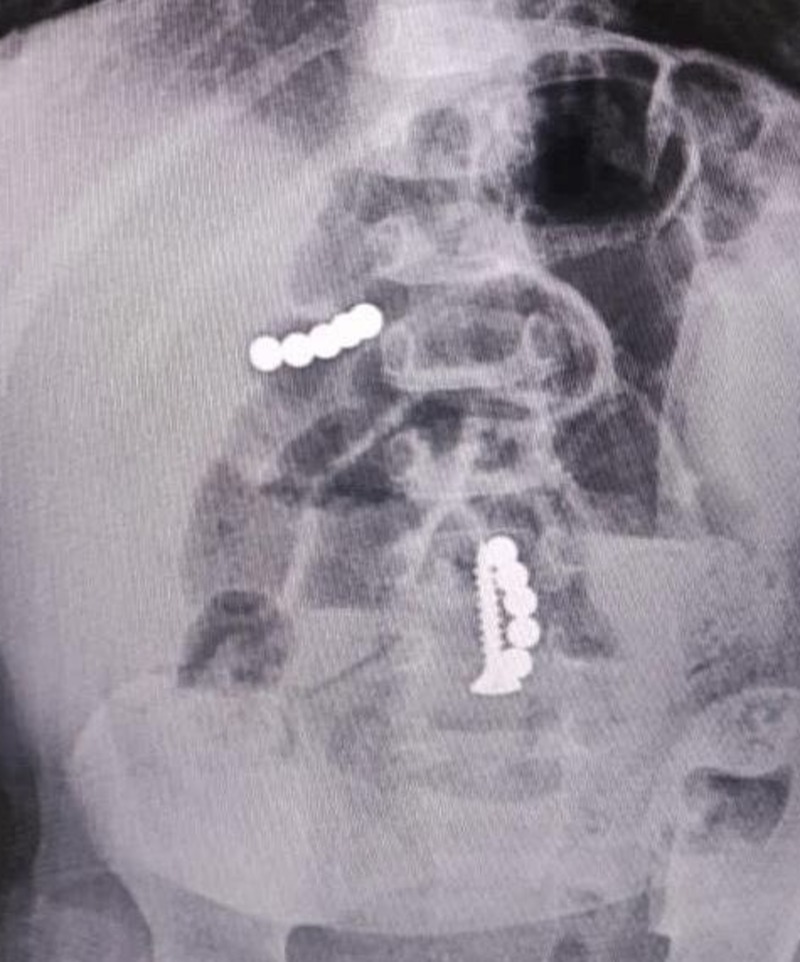

На  скорой ребёнка отвезли в  детскую краевую больницу. Дежурный врач, несмотря на  отсутствие прямых признаков хирургического заболевания, всё  же решил сделать малышу рентгенографию брюшной и  грудной полости. На  снимках он  увидел множество магнитов и  саморез в  желудке и  кишечнике пациента.

Хирурги провели экстренную операцию. Из  тела малыша извлекли инородные тела. В  месте наибольшего изменения кишечной стенки подвздошной кишки после устранения заворота произвели резекцию (частичное удаление  — прим. ред). После операции ребёнок пять дней находился в  реанимации. Сейчас его выписали, он  чувствует себя лучше.